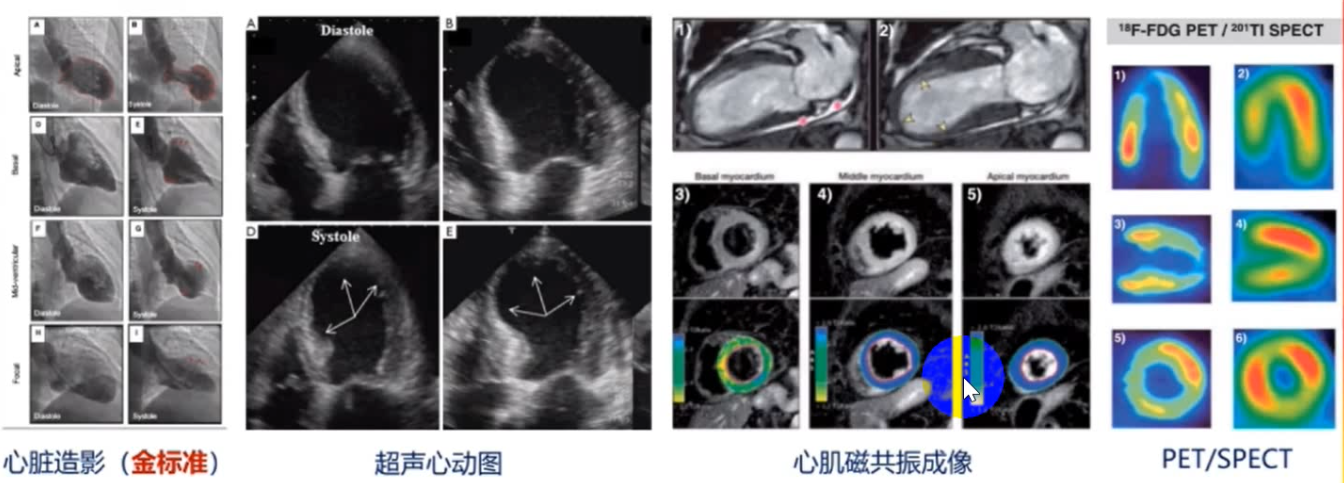

3.影像學檢查

影像學檢查是TTS的重要檢查手段,包括心臟造影、

圖2 TTS的影像學檢查

此外,TTS患者的運動能力、能量學和心臟功能異常也可以通過影像學手段進行測量。